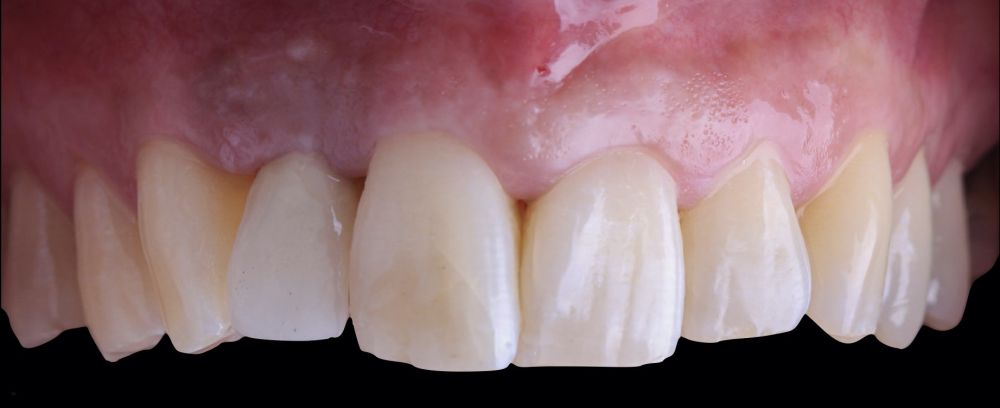

1.2 Treatment

• Phase I: atraumatic extraction of the root remnant 1.2 was performed, followed by curettage of the granulation tissue. Subsequently, the alveolus was filled with an inorganic bovine bone graft (0.25–1mm) combined with autologous platelet- and leukocyte-rich fibrin. Finally, the edges were approximated and sutured with four simple stitches from the vestibular mucosal margin to the palatal aspect. Subsequently, the patient continued using her removable partial denture as a provisional restoration (Figure 1).